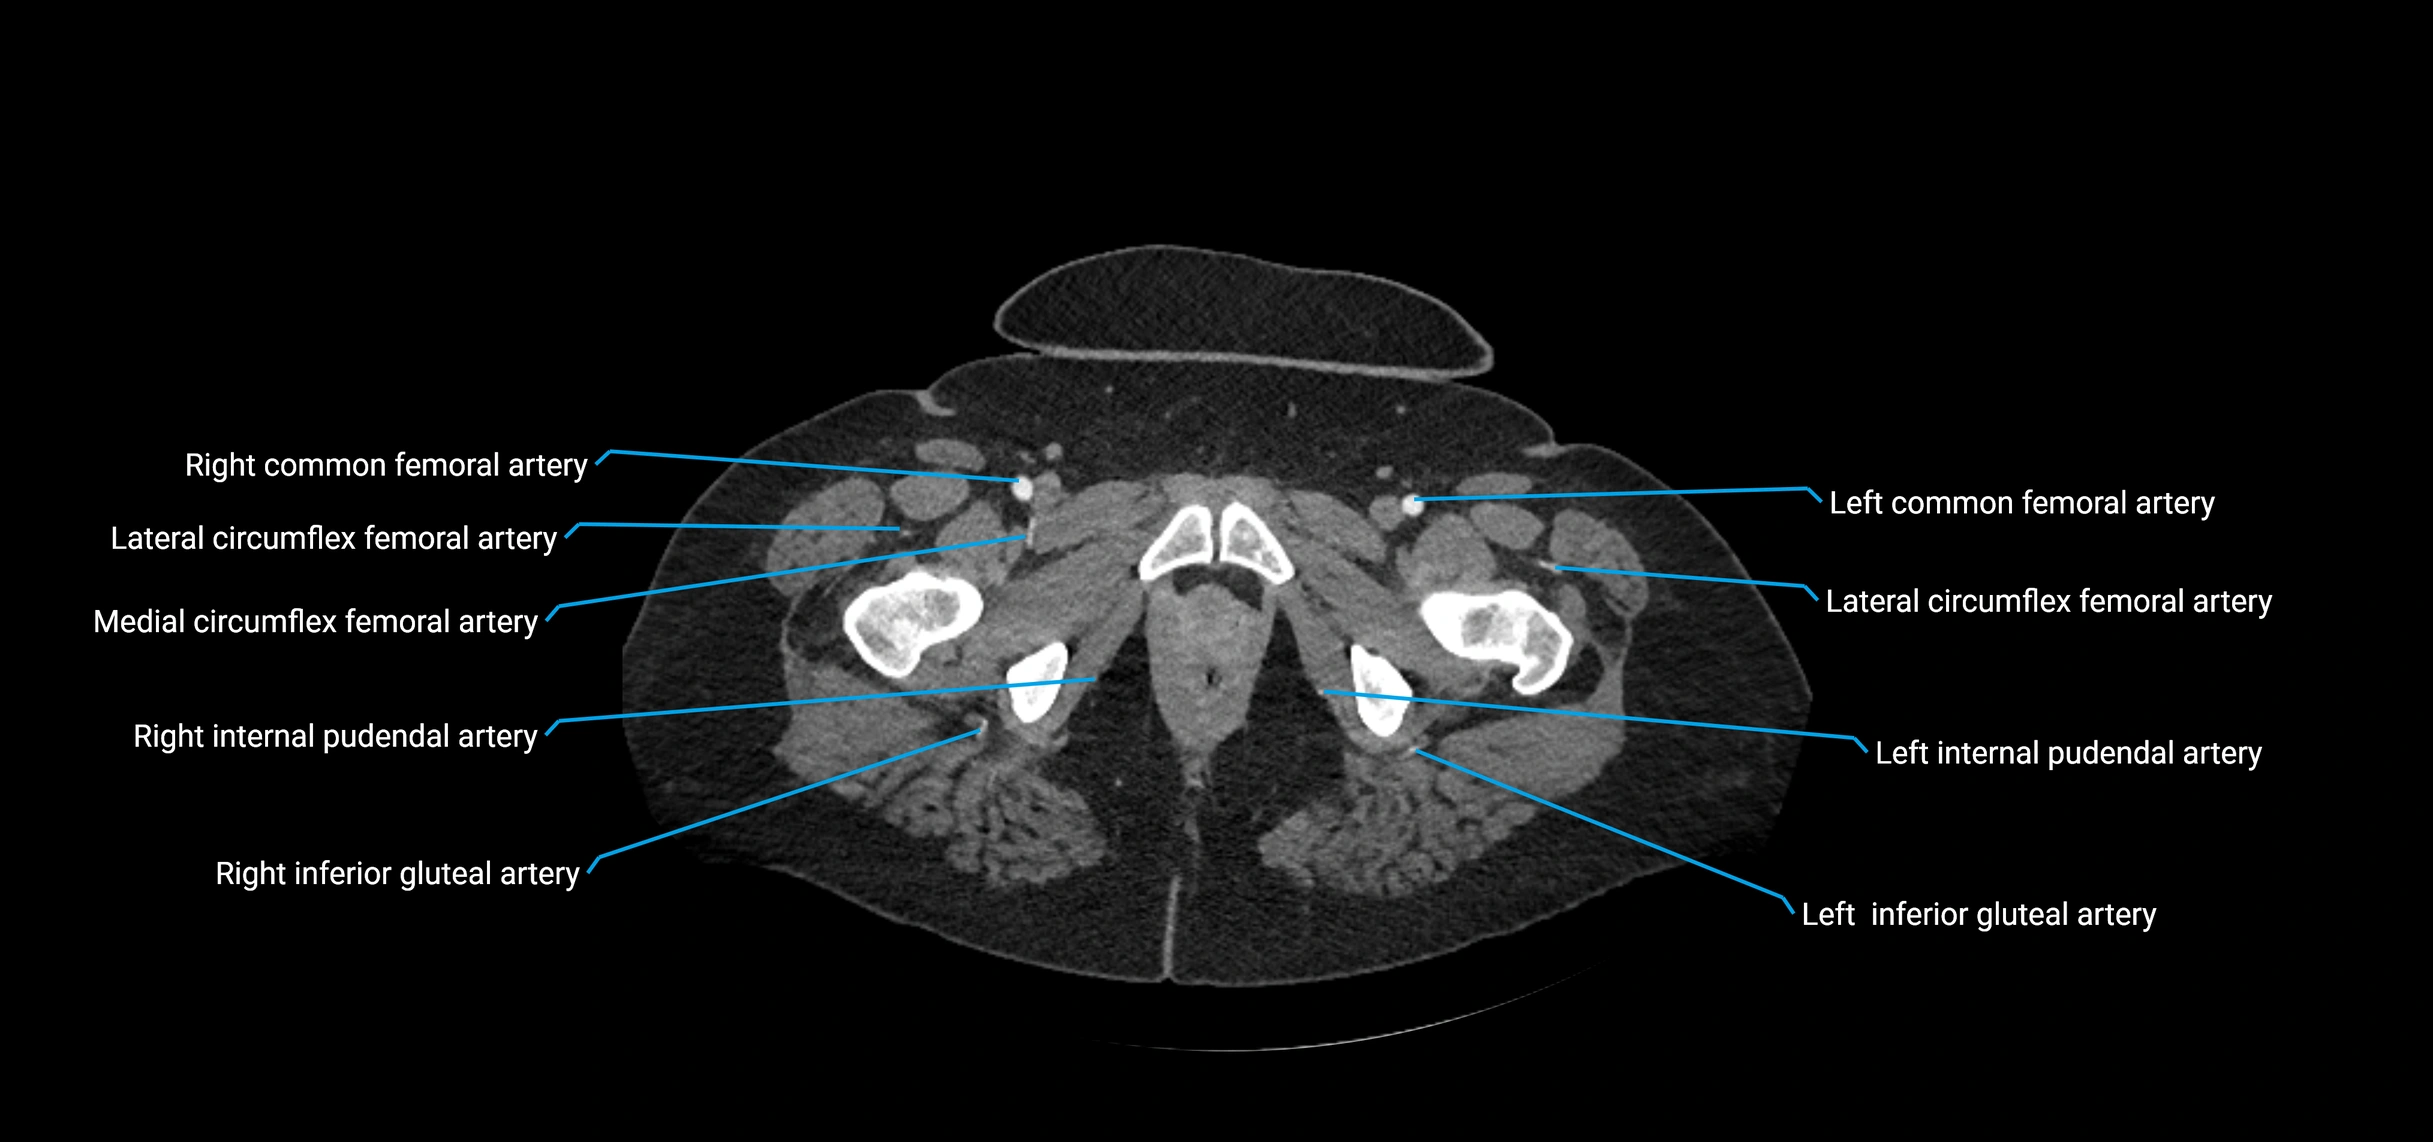

Contrast-enhanced CT (CTA):

• Gold standard for abdominal aortic imaging

• Provides excellent detail of lumen, wall, aneurysm, thrombus, and branch vessels

• Multiplanar and 3D reconstructions help in aneurysm measurement, stent graft planning, and dissection evaluation

• Detects acute rupture, traumatic injury, or occlusion with high sensitivity